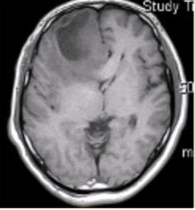

患者女,68岁。头痛、恶心2周,加重2d。头CT显示如下图。

可能的诊断是(提示头颅CT增强及CT灌注成像(脑血流量及表面渗透值明显升高)显示如下图。)()

关于该病的描述,正确的是()

CT、MR支持病变位于轴外的征象是()

A.6h以内